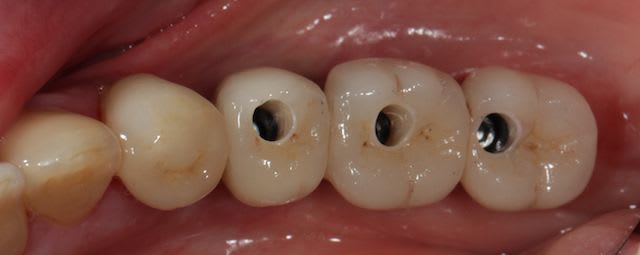

Bon ben voilà c'est fini, reste plus qu'a faire l'autre coté ;)

Img 4431 so0uck - Eugenol

Img 4427 vd1sxf - Eugenol

Versini gs7unb - Eugenol

Img 4430 pddcyk - Eugenol

Photo 158 mluhia - Eugenol